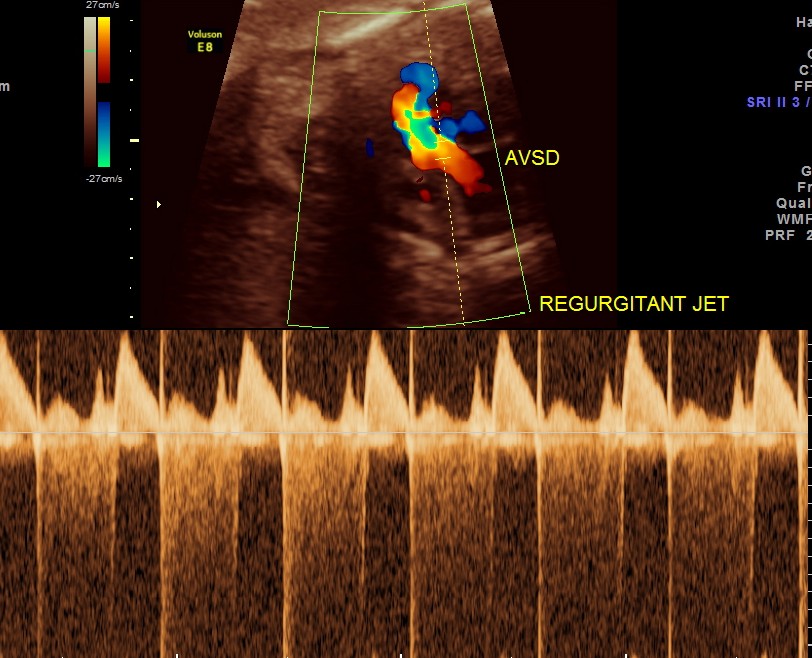

A V VALVES are at the same level

STIC image shows ATRIO VENTRICULAR SEPTAL DEFECT ( ENDOCARDIAL CUSHION DEFECT )

The next image shows spectral doppler showing prominent regurgitant jet in A V SEPTAL DEFECT

4. Prominent regurgitant jet seen at A V septal defect